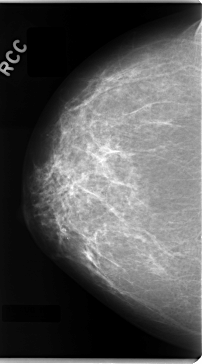

C_0089_1.RIGHT_CC

RIGHT_CC LINES 4728 PIXELS_PER_LINE 2624 BITS_PER_PIXEL 12 RESOLUTION 50 NON_OVERLAY